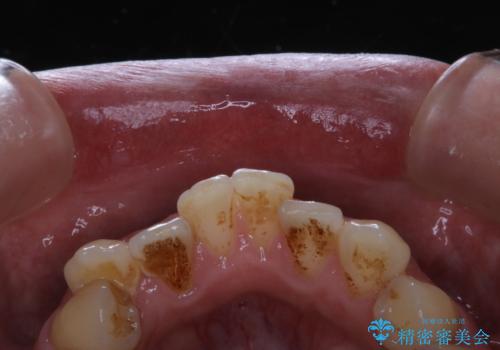

タバコのヤニをPMTCできれいに

- タバコによる着色が気になるため、全て取りたいとのことで来院されました。PMTC60分コースを行いました。

タバコに含まれているものの中で、タールというものが歯の着色の原因です。その、タールによって付着してしまった着色はご自身で落とすことはできません。